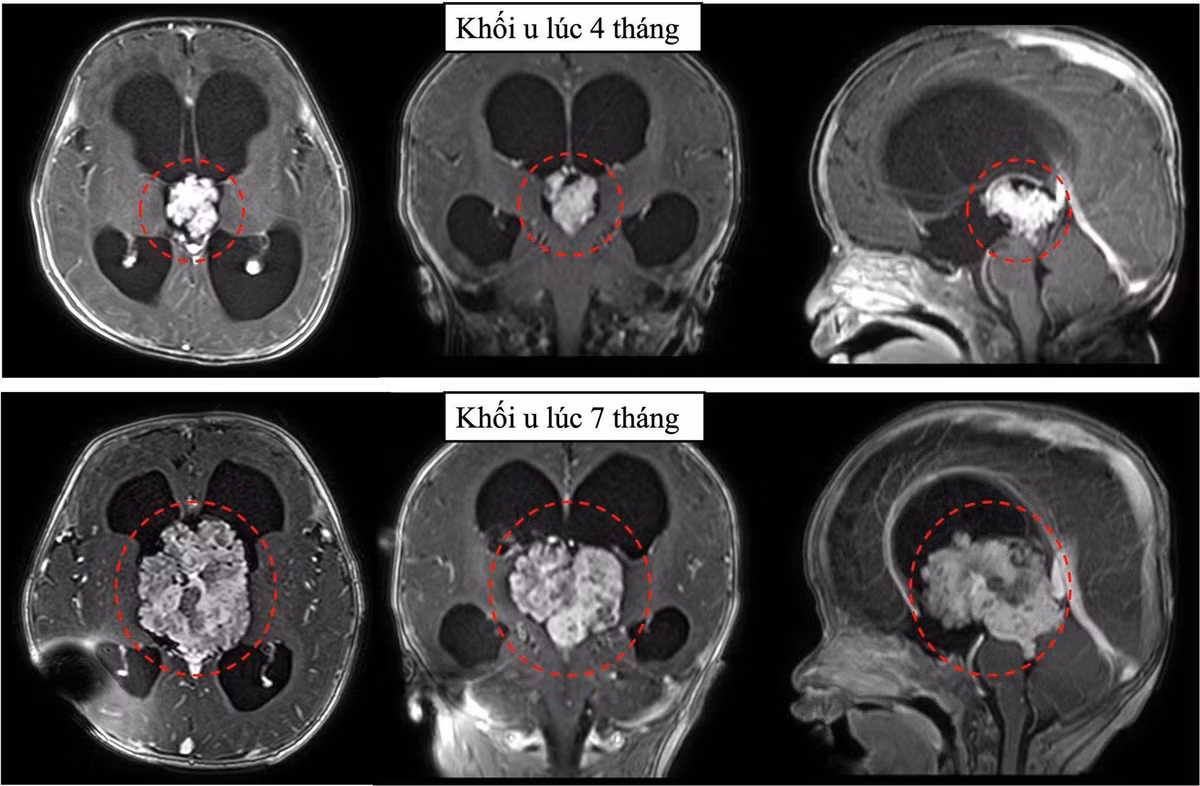

Khối u vùng não thất III lúc 4 tháng tuổi và 7 tháng tuổi của bé G.K.

3 tháng u tăng kích thước gấp 3 lần

Tuy nhiên, phim cộng hưởng từ sọ não 3 tháng sau cho thấy u phát triển rất nhanh, tăng kích thước hơn gấp 3 lần. Không thể trì hoãn thêm, bác sĩ khoa ngoại thần kinh đã tư vấn gia đình bé phẫu thuật mổ lấy u để kịp thời cứu bé.